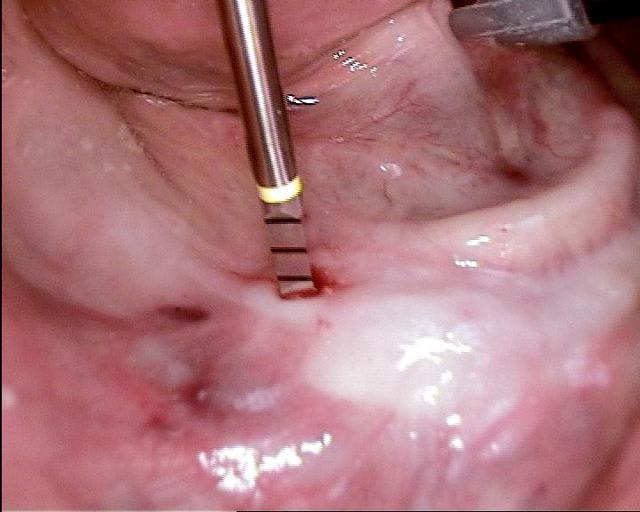

Les forets utilisés ont 3 faces et sont coniques (250 trs/min) permettent une condensation de l´os et un traitement minimalement invasif.